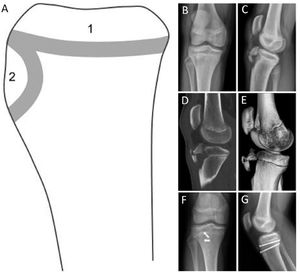

La clasificación más utilizada para describir los meniscos discoideos es la de Watanabe, que agrupó esta variante anatómica en 3 tipos según su porcentaje de cobertura del platillo tibial y su estabilidad18 (Figura 2). En muchos casos, el menisco discoideo se presenta de forma asintomática y puede ser solo un hallazgo imagenológico o intraoperatorio16,19. Sin embargo, en pacientes que presentan síntomas, estos pueden ser secundarios a la inestabilidad o a la presencia de roturas meniscales. La presentación clínica va a depender de la edad, siendo más frecuente que la inestabilidad produzca síntomas más precoces, en niños menores a 10 años, mientras que las roturas ocurren con mayor frecuencia en pacientes más cercanos a la adolescencia. Aquellos meniscos inestables, suelen producir un resalte lateral a la movilidad de la rodilla, que puede ser eventualmente doloroso, y presentar un bloqueo a la extensión completa de la rodilla. Las roturas de un menisco discoideo producen síntomas mecánicos, que pueden ser de inicio insidioso, caracterizados por dolor a la carga y movilidad de la rodilla y derrame articular20,21.

Clasificación de Watanabe para menisco lateral discoideo. (A) Tipo I, Discoideo completo. (B) Tipo II, Cobertura incompleta de la superficie tibial (no más del 80%) estable a la palpación, con inserciones coronales. (C) Tipo III (Variante Wrisberg), normal o forma levemente discoide con inestabilidad debido a ausencia de fijación coronal posterior, solo mantiene el ligamento de Wrisberg. (Ref. 24).

La RM es el examen fundamental para confirmar la sospecha diagnóstica, permite determinar la morfología del menisco, diagnosticar roturas asociadas y orienta a la presencia de inestabilidad22 (Figura 3).

Signos imagenológicos y visión artroscópica de menisco discoideo. (A) Proyección radiográfica anteroposterior (AP) de rodilla sin carga con menisco discoideo lateral. Se observa un aplanamiento del cóndilo femoral lateral, un aumento del espacio articular y una deformidad del platillo tibial lateral en forma de “copa”. (B, C) Resonancia magnética (RM) de rodilla, cortes coronal y sagital T1 y FAT SAT confirmando un menisco lateral discoideo completo con un aumento de señal intrasustancia sugiriendo una degeneración mixoidea del menisco. (D) Imagen artroscópica de el mismo paciente, a la izquierda el menisco discoideo completo, y luego a la derecha la imagen final tras realizar un tallado meniscal artroscópico.

La historia natural de un menisco discoideo asintomático es desconocida, por lo tanto, la indicación es sólo observarlos. En aquellos pacientes con diagnóstico incidental o mínimos síntomas, la indicación es el manejo conservador con seguimiento periódico y consulta precoz en caso de síntomas23. El tratamiento quirúrgico se reserva para aquellos pacientes sintomáticos, que se presentan con dolor, derrame, pérdida del rango articular y limitación de sus actividades. El objetivo del tratamiento quirúrgico es lograr un menisco con una forma lo más similar a la normal, estable y sin roturas. La cirugía se realiza por vía artroscópica, mediante un “tallado” meniscal, que busca resecar el excedente meniscal anómalo, preservando un reborde periférico de 6-8mm (Figura 3). En el mismo tiempo quirúrgico se resecan o reparan las roturas meniscales, y se estabiliza la periferia del menisco con suturas en caso inestabilidad o hipermovilidad patológica16,24.